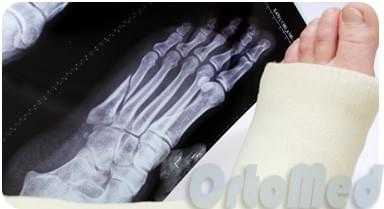

Рентгенограмм в 2-х проекциях обычно достаточно, чтобы диагностировать перелом. Но при стресс-переломах без смещения, иногда, их невозможно определить даже очень опытному врачу.

В таких случаях назначаются контрольные рентгенограммы через 10-14 дней, когда происходит резорбция костной ткани в месте перелома. Так же стресс переломы трудно увидеть на рентгеновских снимках, пока они не начали срастаться и не начала образовываться костная мозоль. Как раз её очень хорошо видно на рентгенограммах. Компьютерная томография или МРТ могут быть необходимы для исключения стресс перелома и других патологий стопы.